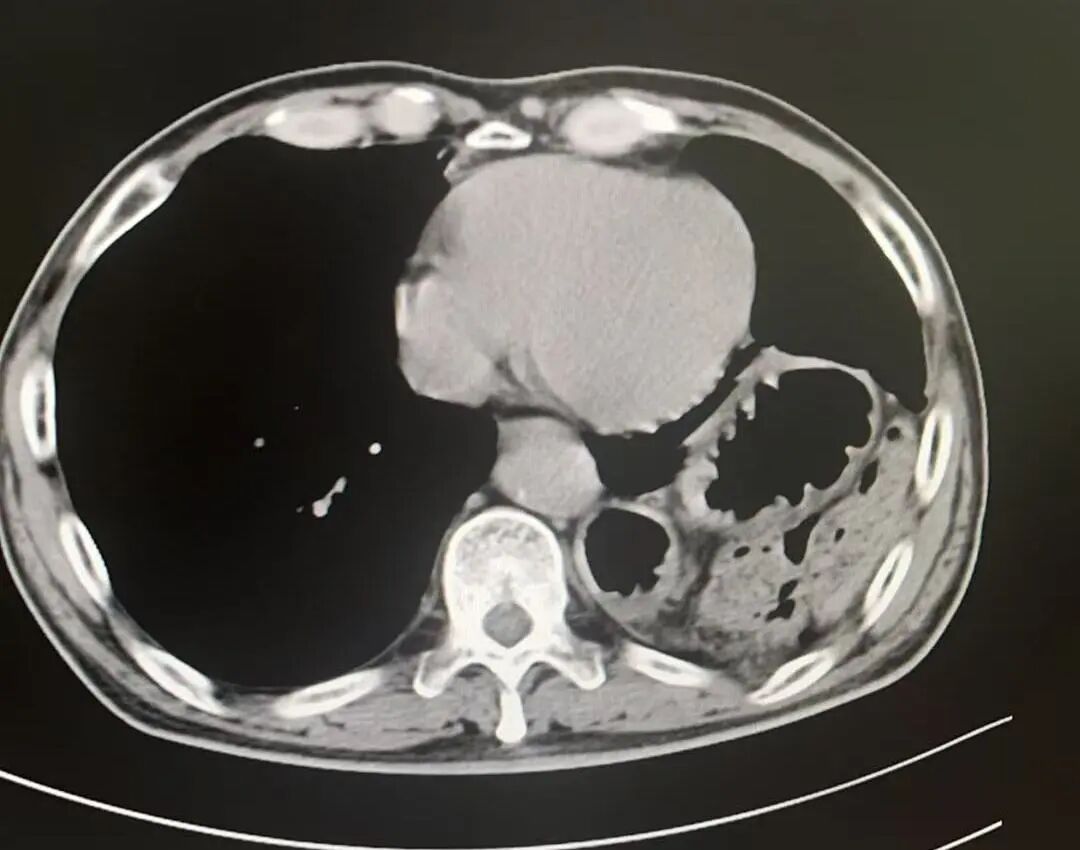

术后影像

膈疝修补如拆“定时炸弹”,需松解粘连、归位脏器、修复缺损三步精准到位。团队采用阶梯策略,在确保手术效果的同时最大程度降低风险、减少创伤。术后,刘大爷的症状迅速缓解,现已康复出院,重归正常生活。